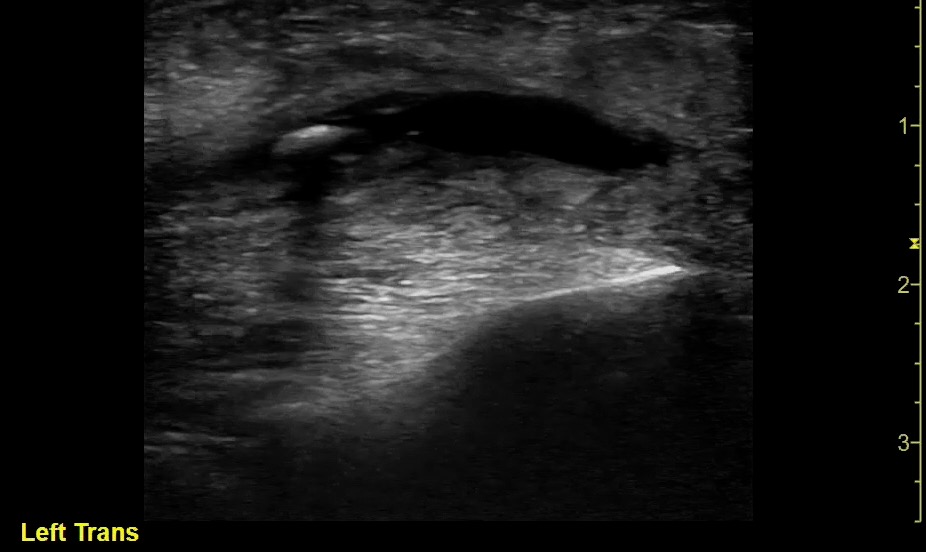

- Submandibular gland sialoadenitis/sialolithiasis:

- Appears heterogeneous with dilatation of the salivary ducts.

- Increased vascularity can be seen on Doppler.

- Pus and debris may be visualized at the Wharton’s duct ostium in the floor of the mouth.

- Submandibular gland stone appears hyperechoic with distal acoustic shadowing.